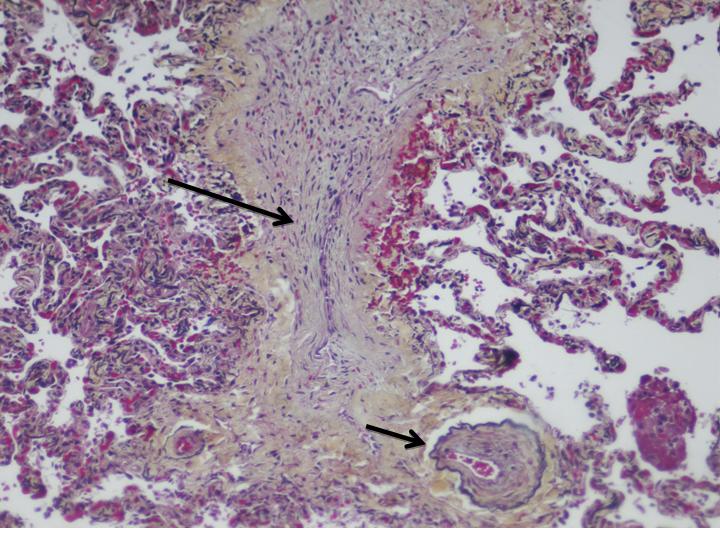

Figure 2: Pathology. Interlobular septal vein showing complete occlusion (arrow). Note the partial occlusion in the branch extending into alveolated tissue (short arrow) outlined by the Movat stain.

Figure 3: Pathology. Large pulmonary vein showing complete luminal obliteration by loose connective tissue, highlighted by a MOVAT stain that outlines the medial elastic tissue.